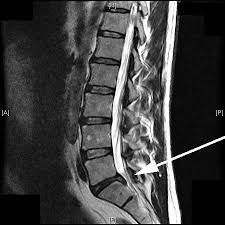

Bandscheiben op lws 4 5. Sie kommen meist zwischen den Wirbeln LWK Lendenwirbelkörper 45 und LWK 5SWK 1 Sakralwirbelkörper vor an der vorletzten und letzten Bandscheibe. Bandscheibenvorfälle sind Teil einer natürlichen Abnützung des Gewebes. Drückt der Gallertkern auf einen Rückenmarksnerven leiden Betroffene unter starken Rückenschmerzen die teilweise bis in Arme und Beine ausstrahlen.

Ursachen Diagnose und Therapie. Wie der Bandscheiben-Vorfall Prolaps ist die Bandscheiben-Vorwölbung Protrusion besonders häufig in der Etage bei L4L5 zwischen dem 4.

Wenn die Physiotherapie und Medikamente nicht mehr helfen und die Schmerzen zu stark sind oder wenn der Druck auf die Nerven Ausfälle verursacht Taubheit Muskelschwäche Lähmung sollte eine Operation in Betracht gezogen werden. Bandscheibenvorfall LWS Übungen - Hier findest du 5 effektive Übungen bei einem Bandscheibenvorfall in der Lendenwirbelsäule inkl. Es geht mir zur Zeit nicht gut mache mir auch große Sorgen wie es wird in den nächsten Tagen und Wochen mit den Schmerzen und Beschwerden. Ich wurde am 4. Frank aus München in. Probieren Sie es selbst aus. Sie kommen meist zwischen den Wirbeln LWK Lendenwirbelkörper 45 und LWK 5SWK 1 Sakralwirbelkörper vor an der vorletzten und letzten Bandscheibe. Die Bandscheiben der Wirbelsäule übt eine Art Stossdämpferfunktion aus und dient der Elastizität und der Beweglichkeit der Wirbelsäule. Lendenwirbel und dem 5.

Die Bandscheibenvorfälle an der Lendenwirbelsäule sind die häufigsten Bandscheibenvorfälle an der Wirbelsäule. In der Regel verschwinden die Schmerzen zwar nach der OP es kann aber immer sein dass sich Symptome nicht zurückbilden. Wenn die Physiotherapie und Medikamente nicht mehr helfen und die Schmerzen zu stark sind oder wenn der Druck auf die Nerven Ausfälle verursacht Taubheit Muskelschwäche Lähmung sollte eine Operation in Betracht gezogen werden. 3053 Beiträge ø047Tag Hallo vor 1 Woche hatte ich eine große Bandscheiben-OP. Wie der Bandscheiben-Vorfall Prolaps ist die Bandscheiben-Vorwölbung Protrusion besonders häufig in der Etage bei L4L5 zwischen dem 4. Bandscheibenvorfall 4-5 Lendenwirbel Hey S-A2011 danke für Deine Erzählung. Alleine in Deutschland werden jährlich ungefähr 150000 Bandscheibenvorfälle operativ behandelt.